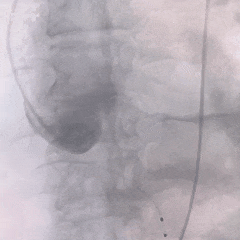

术中影像

8mm外周球囊扩张髂动脉狭窄处

根部造影可见大量反流